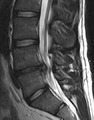

• Magnetic resonance imaging (MRI) without contrast is a diagnostic test that produces three-dimensional images of body structures using powerful magnets and computer technology. It can show the spinal cord, nerve roots, and surrounding areas, as well as enlargement, degeneration, and tumors. It shows soft tissues better than CAT scans. An MRI performed with a high magnetic field strength usually provides the most conclusive evidence for diagnosis of a disc herniation. T2-weighted images allow for clear visualization of protruded disc material in the spinal canal.